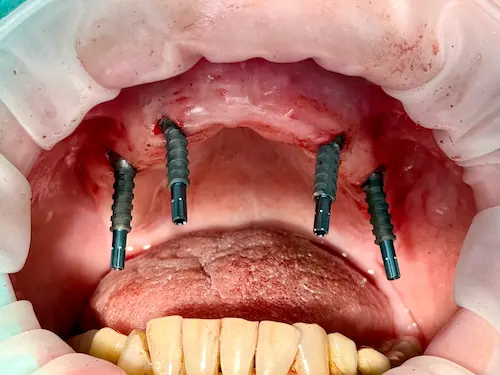

All-on-4 ® – Patientenfall

Bei Zahnlosigkeit oder nicht mehr erhaltungswürdigen Zähnen wünschen sich die Patient*innen der Praxisklinik Herne natürlich zeitnahe und minimalinvasive Lösungen. Dank des All-on-4 ® / All-on-6 ®–Konzepte können wir ihnen diesen Wunsch oftmals innerhalb nur eines einzigen Behandlungstages erfüllen: 4 bzw. 6 Zahnimplantate werden gesetzt und bilden im Folgenden die Grundlage für den passenden festsitzenden oder herausnehmbaren Zahnersatz. Die einzelnen Behandlungsschritte veranschaulichen wir Ihnen anhand eines aktuellen Patientenfalls aus diesem Jahr.

Der Patientenfall

Unser 55-jähriger Patient stellte sich uns nach Jahrzehnten der Nichtbehandlung mit einen stark kariösen und nur zum Teil bezahnten Kiefer vor. Aufgrund einiger abgebrochener Zahnwurzeln wurde schnell ersichtlich: Der bisherige Zahnersatz kann nicht erneuert werden; außerdem wünschte sich unser Patient in Zukunft einen gaumenfreien festsitzenden Zahnersatz. Alles deutete Richtung All-on-4 ® / All-on-6 ®–Konzept.

Der chirurgische Eingriff im Detail

Der Tag der Operation ist gekommen: Im ersten Schritt werden die noch vorhandenen Zähne gezogen sowie die Wurzeln und vereinzelte Zysten restlos entfernt. Dies erwies sich im vorliegenden Fall als extrem komplex und folgenreich: Beim Extrahieren gingen Teile der Knochenwände verloren, was einen deutlichen Mehraufwand beim Aufbau des Kieferkamms nach sich zog. Zuzüglich zu Knochenersatzmaterial verwendete Dr. Mintert dafür 2 Collagen Blöcke, 2 Membranen und 0,3 ml Emdogain. Letzteres dient der Entwicklung von zahnstützendem Gewebe. Auch Eigenknochen aus einem zweiten OP-Gebiet kam zum Einsatz. Im Oberkiefer wurde außerdem ein sogenannter Sinuslift durchgeführt, der – vereinfacht gesprochen – die Kieferhöhlen anheben soll. Nun waren die Grundlagen für den nächsten Schritt geschaffen: Eine eigens angefertigte Bohrschablone ermöglicht die navigierte Implantation. So fanden alle acht Implantate trotz ungeplanter Komplikationen ihren rechten Platz im Mundraum. Abschließend wird L-PRF Plasma, d.h. zentrifugiertes Eigenblut eingebracht, um die Wundheilung zu unterstützen. Als Zahnersatz werden zwei festsitzende Keramikbrücken gewählt und auf künstliche Keramikaufbauten geklebt. Diese wiederum sind mit jeweils vier Implantaten verschraubt.